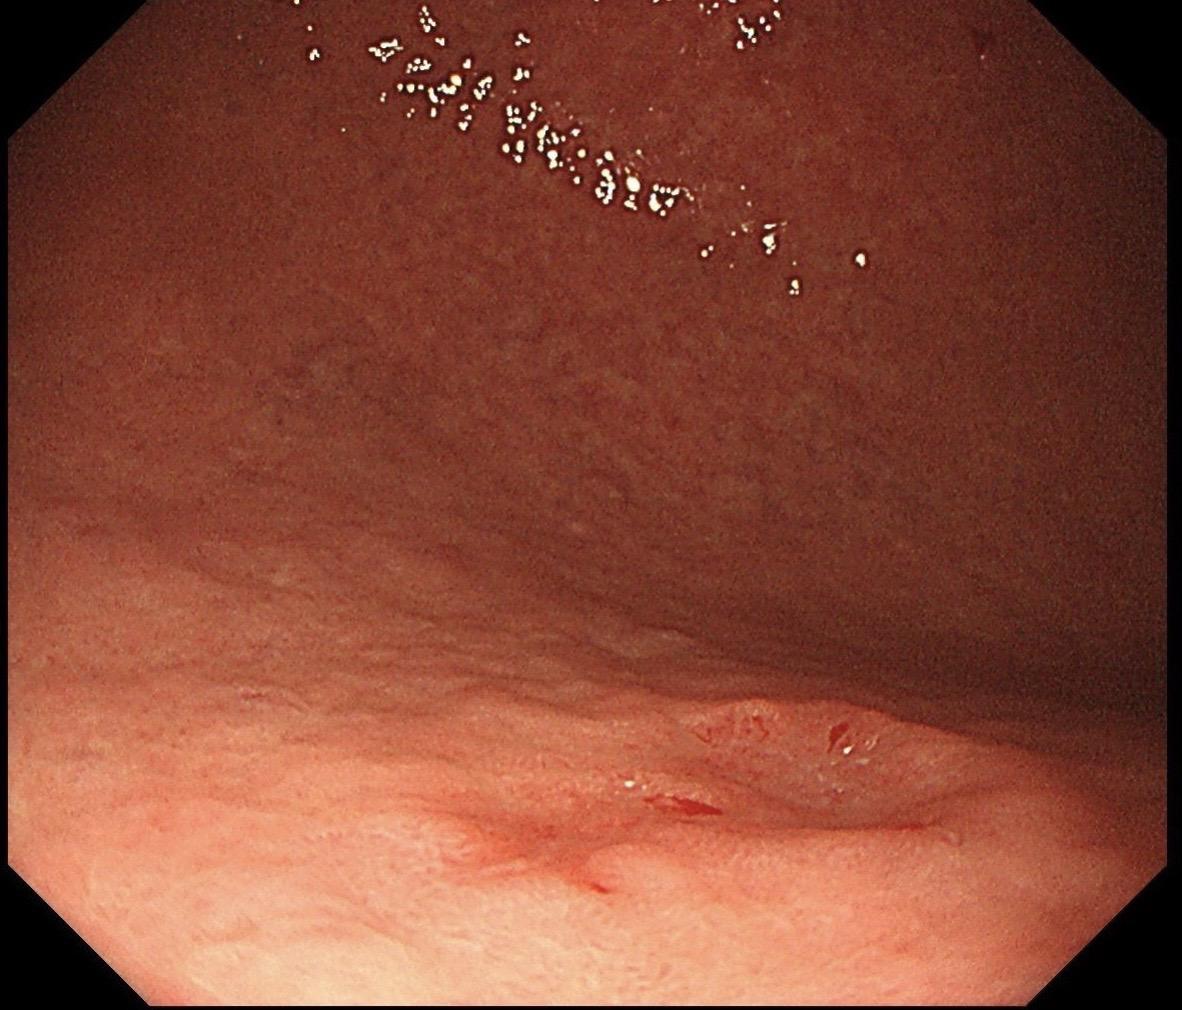

男,70岁,胃底体双发病变。看图猜猜病理呢……尤其胃底这个小的~凹陷性病变,当中央结构观察欠清时,边缘的异常微血管往往有提示作用,哪怕是局部。两处都考虑早期病变,拟ESD微创治疗。